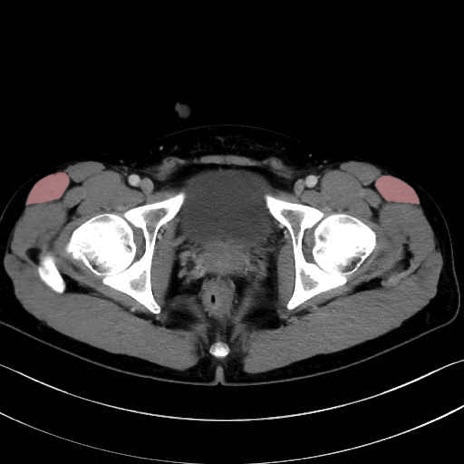

大腿筋膜張筋 (Tensor fasciae latae)